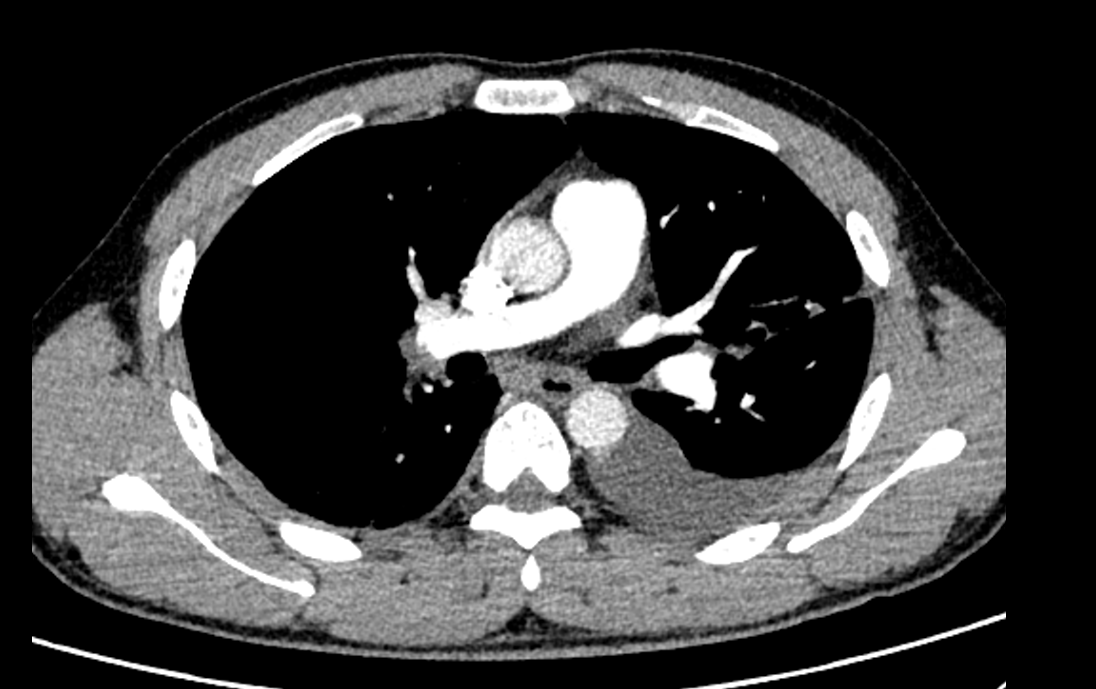

术前心率100次/分左右,SPO296%,术中肺动脉压40/20(27)mmHg,术后心率降至84次/分左右,SPO2升至98%;术后患者胸闷不适症状完全消失,复查CTPA示双侧肺动脉充盈缺损显著缩小,血栓负荷显著下降,术后心脏彩超估测SPAP 22mmHg,活动后无不适,快速改善症状,显著缩短住院时间。

术前、术后CTPA